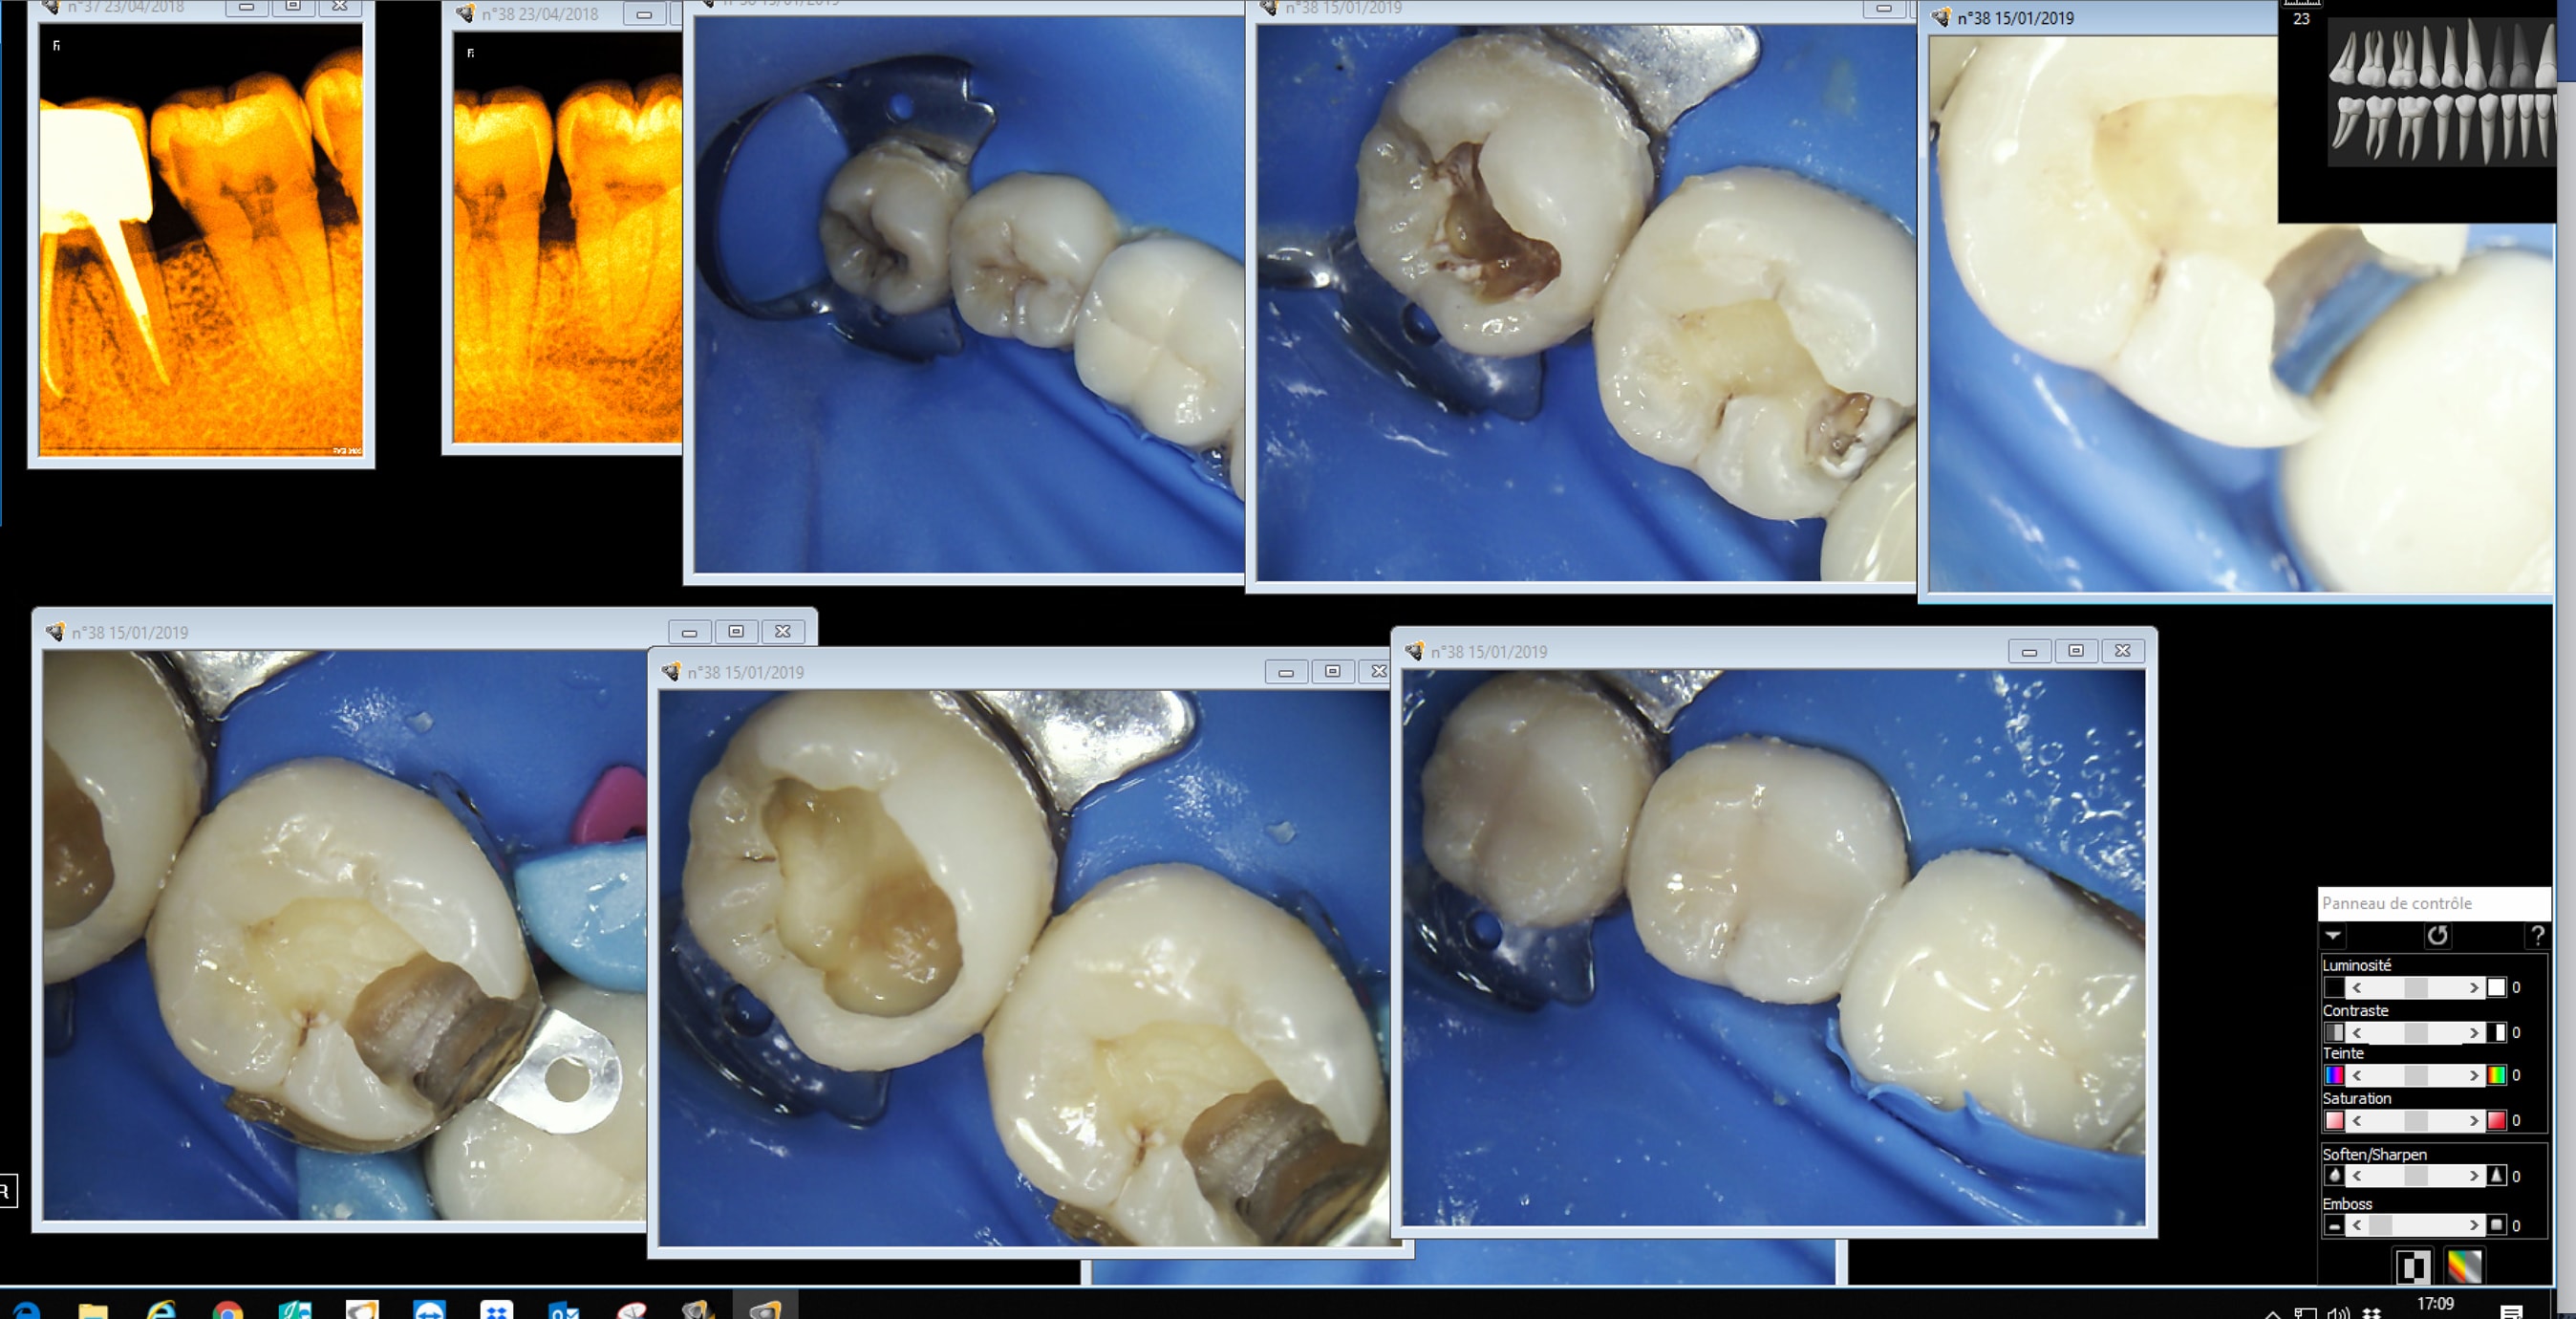

Capture d écran 2019 01 15 17.09 - Eugenol